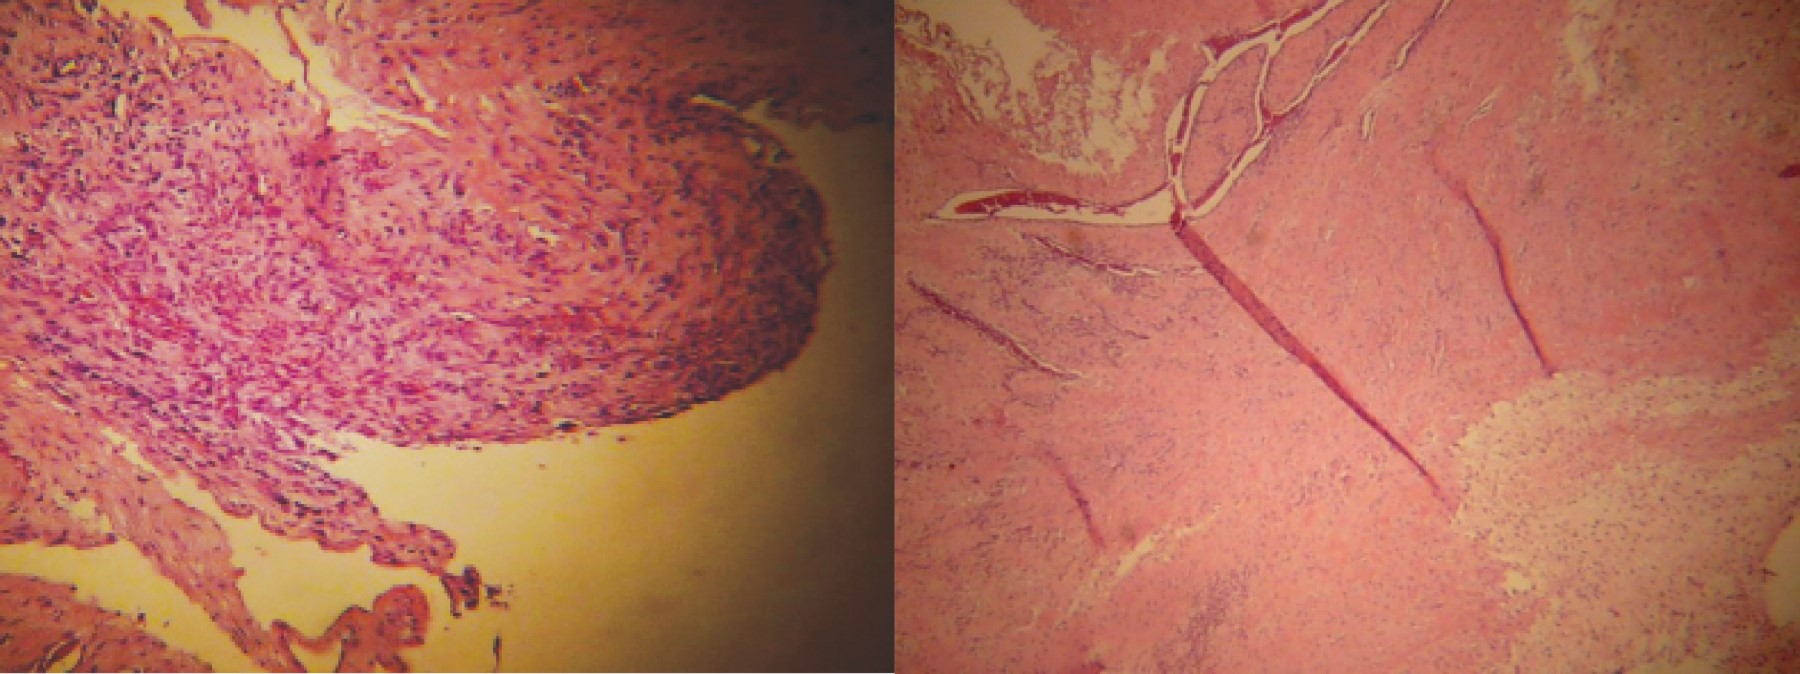

El paciente evolucionó estable, sin palpitaciones, no refirió disnea; mencionó mejoría sintomática en comparación a estado preoperatorio. Se inició y progresó la vía oral a las 24 horas posterior a procedimiento; gasto de drenaje abdominal serohemático en los primeros días. El control radiológico, radiografías de abdomen de pie y decúbito mostraron adecuada distribución de gas intestinal. El paciente se egresó de la unidad al tercer día después del procedimiento quirúrgico, enviando a la consulta externa hospitalaria para seguimiento y control. Su evolución a mediano plazo, al año de seguimiento, con aumento ponderal y sin evidencia clínica de recurrencia de sintomatología obstructiva intestinal. Reporte histopatológico: quiste mesotelial tipo seroso, epiplón, con proceso inflamatorio crónico moderado. Líquido peritoneal, con proceso inflamatorio crónico moderado (Figura 4).

Desde su descripción inicial en 1907 como PCEE y de la denominación de abdomen en capullo por Foo en 1978, se han presentado alrededor de 50 casos en la literatura. Debido a las características histológicas de la PCEE o AC se ha sugerido estar ligada a procesos inflamatorios crónicos de la cavidad abdominal, manifestándose como tejido mesenquimatoso con reacción inflamatoria con presencia de células inflamatorias crónicas y agudas. En ocasiones no se puede identificar el factor asociado con su etiología o PCEE idiopática (abdomen en capullo) o ser secundaria a padecimientos diversos.12

El diagnóstico definitivo de esta patología suele ser durante el tratamiento quirúrgico y las características histopatológicas del tejido resecado (Tabla 1).

Figura 4